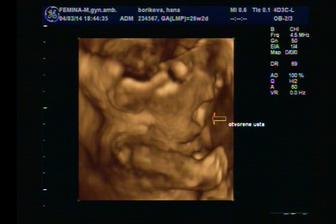

Termín pôrodu máme 8.jún 2014, už aby to bolo 🙂)

@evkasto áno už sa aj mrvíme, podľa Dr. máme aktívne bábo, aj jeho koplo keď nám robil sono 😀